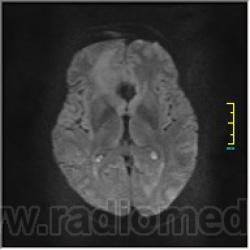

DWI:

Иначе говоря, аневризма с хронической геморрагией, т.к. мы видим фракции крови различного возраста.

Постепенное пристеночное образование тромбов приводит к появлению типичного для аневризмы феномена -слоистости МР сигнала в полости аневризмы. Данная картина демонстрирует слоистый характер тромботических масс в полости аневризмы .Функционрирующая часть имеет низкий сигнал во всех режимах сканирования. Дополнительно-перифокальный отек.

А может более корректно интерпретировать как частично тромбированная аневризма... Уж коь речь идет о фракциях, ну то есть о тромбе по сути.... Ну и плюс перфокальный отек головного мозга (вероятнее цитотоксический+вазогенный).